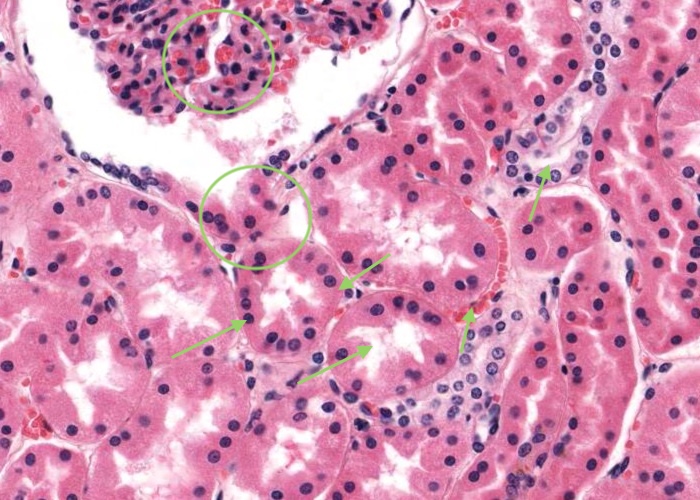

Recall that the proximal convoluted tubule (PCT) originates from the urinary pole as it is the tubule receiving the glomerular filtrate. You can see many profiles of the PCT in this image because it is very tortuous alongside the glomerulus and then will enter a medullary ray as a proximal straight tubule. The cuboidal cells of the PCT have central nuclei and are specialised for absorption and fluid transport so they have many specializations at the ultrastructural level to reflects these functions. For example, their intensely acidophilic cytoplasm reflects abundant mitochondria and they exhibit a "brush border" at their apices and evidence of this is provided in the next item. The lumenal border is rather convoluted and the total diameter of the tubule is greater than that of a distal convoluted tubule. Note the tiny blood capillary surrounding a PCT.

The tall brush border of each proximal convoluted tubule are rich in glycocalyx and therefore, carbohydrate. You may have looked at the brush border during your study of "epithelium" and noted that the brush border is comprised of numerous microvilli extending from the apical surface of the cells.

The distal convoluted tubule (DCT) is a continuation of the distal straight tubule (thick ascending limb of the loop of Henle). The DCT tubule is much less tortuous than the proximal convoluted tubule so you see less profiles of sections of these in the cortical labyrinth. The fluid in the DCT passes into a collecting tubule which in turn empties the fluid into a collecting duct in the medullary ray.